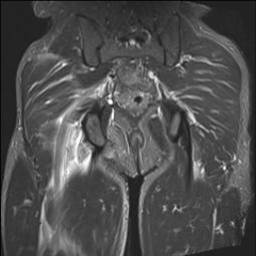

MRI

Complete / retracted tears

Proximal hamstring tear on right (red circle), normal insertion on tuberosity on left (blue circle)

Proximal hamstring tear on right (red circle), normal insertion on left (blue circle)

Proximal hamstring avulsion, with tendon floating in hematoma / seroma